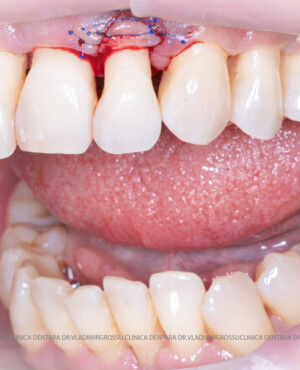

Aditia gingivală este o procedură chirurgicală ce corectează diverse probleme estetice și funcționale, cum ar fi recesiunea gingivală. În implantologia modernă, aditia de țesut moale este utilizată aproape în fiecare intervenție de inserție a implantului dentar pentru a asigura un aspect estetic natural și o bună integrare a implantului în cavitatea bucală.